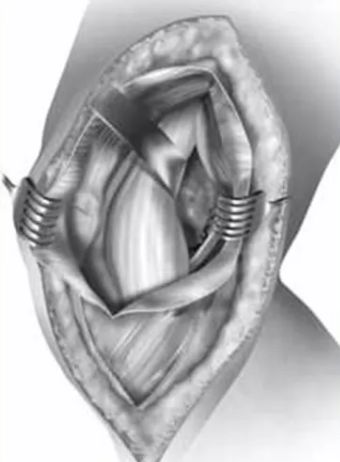

操作:屈膝20°,取膝关节前正中纵行皮肤切口,约25cm长,切开皮下并向内侧游离形成内侧全厚皮瓣,保护隐神经髌下支,显露股内侧肌肌腹,沿股内侧肌和髌腱内侧缘切开深筋膜,尽可能避免结扎膝上内侧动静脉。自膝关节囊和内侧肌间隔游离股内侧肌并向上外侧牵开,于内侧副韧带的股骨内上髁起点前缘到内侧半月板近侧纵向切开关节囊,注意勿损伤内侧半月板,检查半月板有无损伤。将髌骨向外侧牵开显露股骨内侧髁关节面。若骨折线偏后需后前位螺钉固定,进一步屈膝(>120°),在内侧副韧带后侧切开关节囊显露髁后部骨折。

自髌骨上极到胫骨结节做膝关节前正中纵行皮肤切口。

切开皮下并向内外侧游离形成内外侧全厚皮瓣。

显露股内侧斜肌的止点(髌骨内侧缘的中上部)。

切开斜浅面的深筋膜(Subfascial dissection of VMO)。

完全显露股内侧斜肌的止点。

在股内侧斜肌深层放置Z形拉钩,股内侧斜肌的髌骨止点保持完整。

在股内侧斜肌髌骨止点远侧标记缝线。

虚线显示内侧关节囊切开线。

自股骨到股四头肌底面,从内到外切开关节囊,上面的拉钩置于关节囊浅层,下面的拉钩置于关节内。

缝合关节囊,股内侧斜肌完整。

右侧股骨内侧髁,股内侧肌下入路的皮肤和浅层切开。黑线示深筋膜切口:沿股内侧肌和髌腱内侧缘切开,可见隐神经髌下支和膝上内侧动静脉。

股内侧肌向近外侧牵开,显露内侧副韧带浅层,两条黑线显示在内侧副韧带前缘和后缘切开关节囊。

在内侧副韧带后侧切开关节囊显露股骨内髁后部。

在内侧副韧带前缘切开关节囊,可以充分显露骨折块复位和固定。